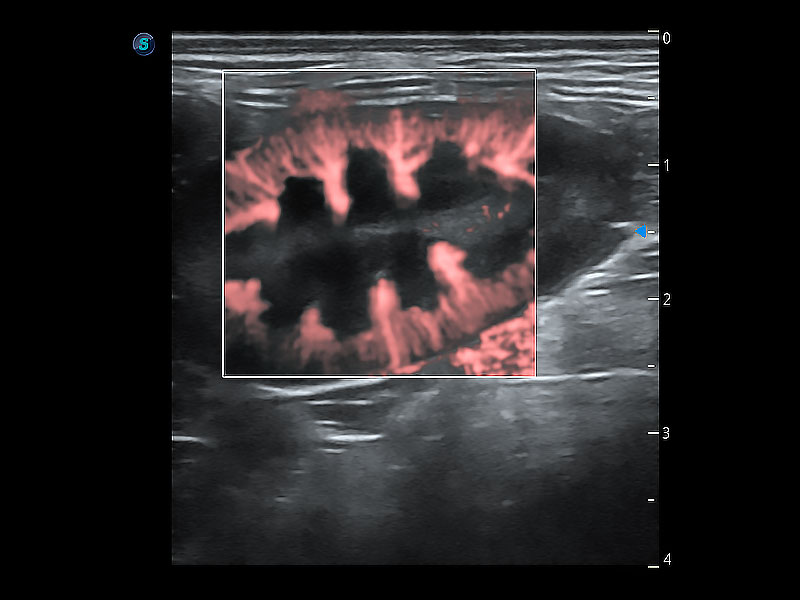

极大提升超低速微细血流的检出能力,同时更精准地滤除软组织和超声信号,为兽用医生提供以往无法通过常规血流获得的疾病诊断信息。

在传统二维血流成像的基础上,呈现血流的立体感,具有动感的生命力之美。即便是微小的血管也能轻松应对,提高了血流的视觉敏感性。

非线性融合造影成像充分利用谐波和基波信号,为难以观察的血流进行增强显像。可用于线阵、凸阵、微凸阵、相控阵探头。